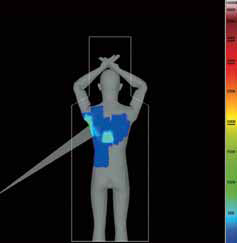

- Dose Tracking System (DTS) – Система стеження за дозою обраховує та відображає в реальному часі дозу на шкіру, отриману пацієнтом. У разі досягнення попередньо заданого критичного рівня дози така система попередження допомагає лікарям уникнути ризику променевого ураження шкіри за рахунок зміни проекції, SID, частоти кадрів.